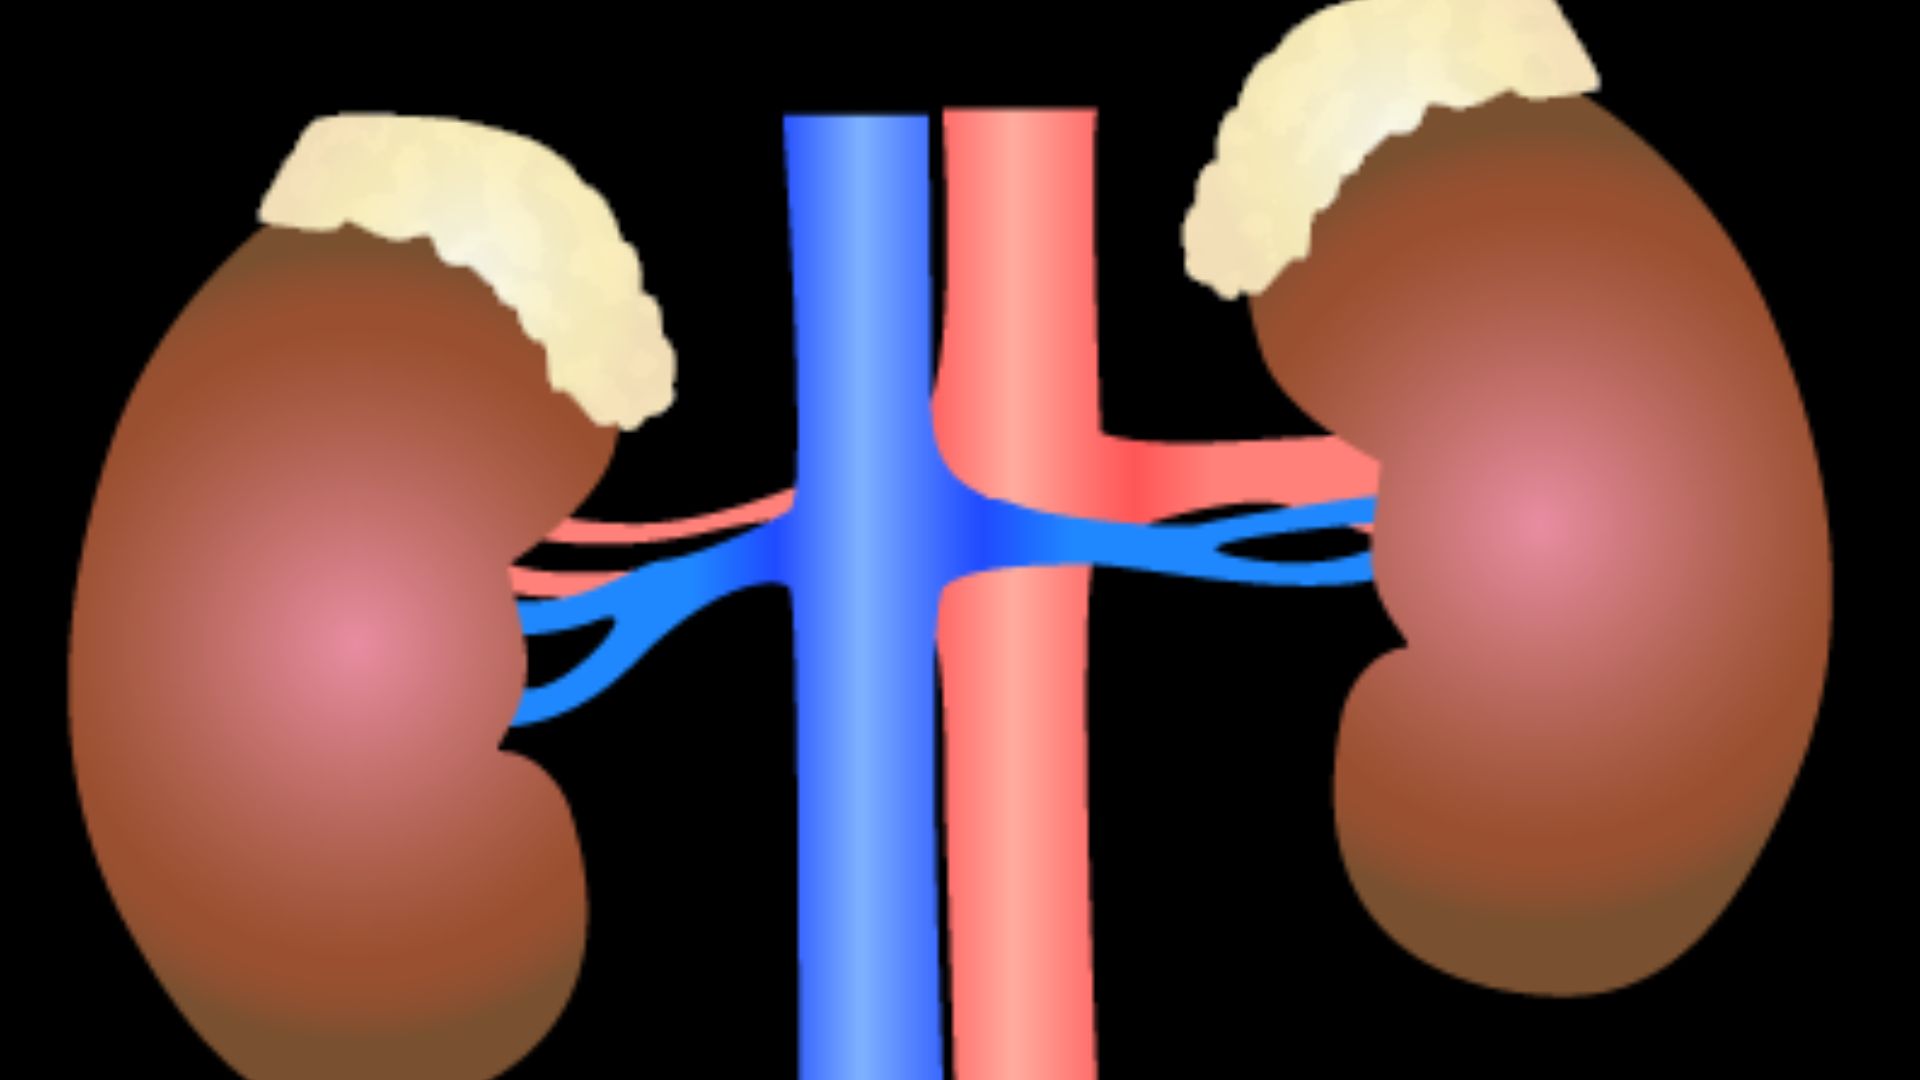

Your Right Kidney Sits Lower Than The Left

DataBase Center for Life Science (DBCLS), Wikimedia Commons